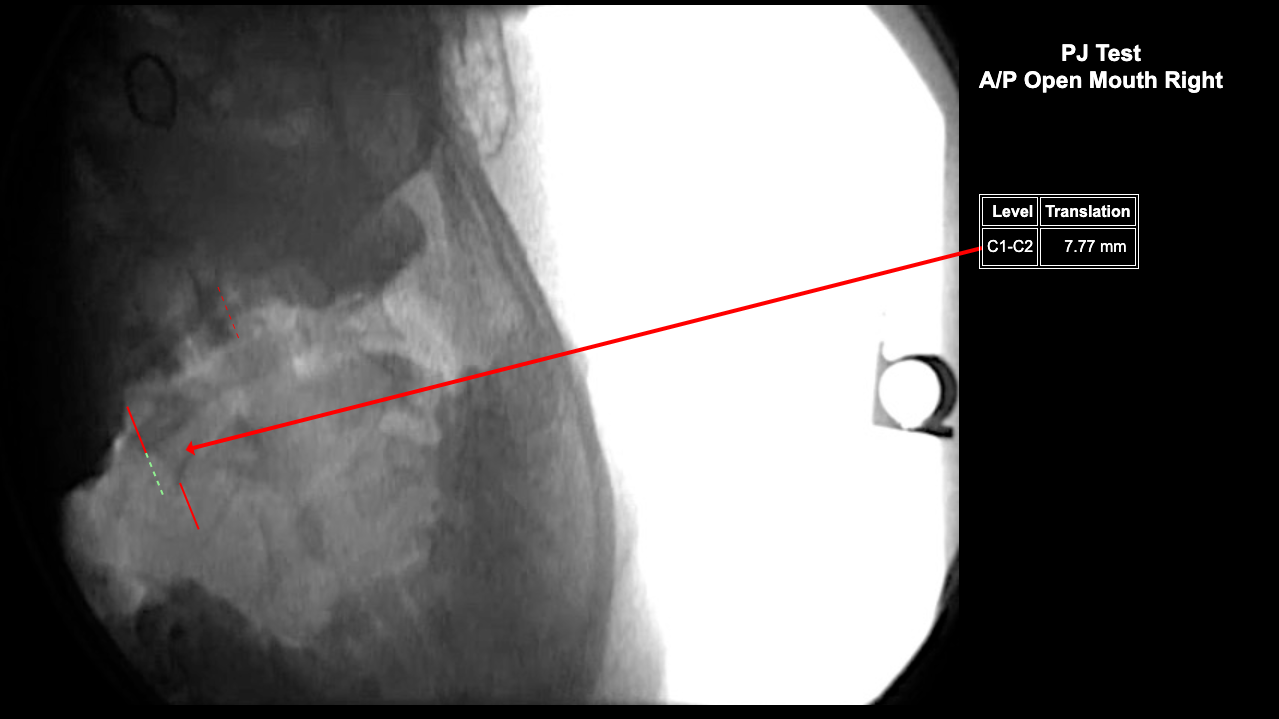

Image Name Image Type Image

Image 2